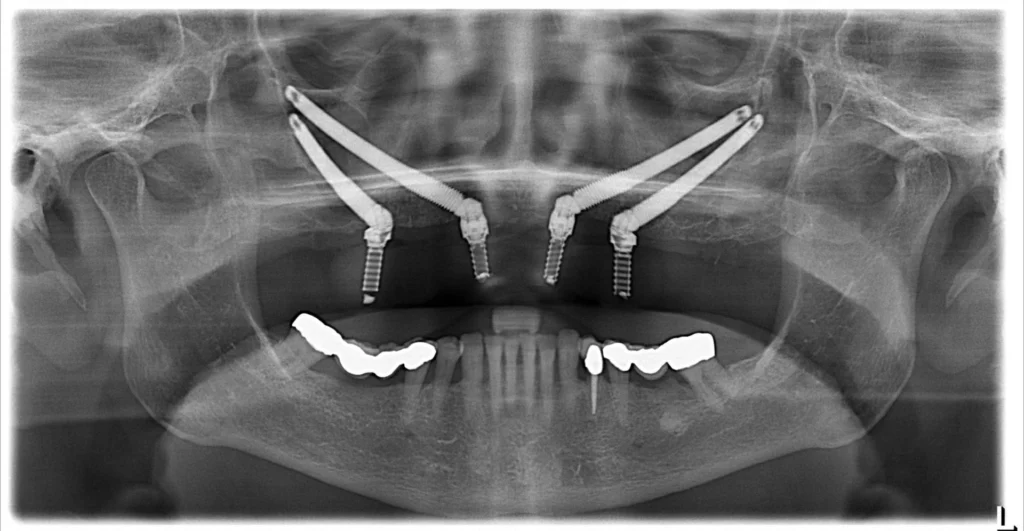

A zygoma dental implant is fundamentally defined as an extra-long dental implant, typically ranging from a considerable 30mm to an impressive 60mm or more in length, specifically engineered to bypass areas of insufficient bone volume in the upper jaw (maxilla) and securely anchor into the consistently dense and robust zygomatic bone, more commonly known as the cheekbone, thereby providing an exceptionally stable and reliable foundation for fixed prosthetic teeth. This definition is absolutely pivotal to truly understanding “What are Zygomatic Dental Implants?” and their unique role in restorative dentistry. Unlike their conventional counterparts, which are shorter and designed for placement within the alveolar bone (the part of the jaw that traditionally holds teeth), zygomatic implants embark on a longer journey, angling through or alongside the maxillary sinus to reach their target in the cheekbone. This unique characteristic makes them the go-to solution in cases of severe maxillary atrophy, where the jawbone has resorbed to such an extent that placing standard implants would be akin to trying to anchor a ship in shallow sand – simply not feasible or reliable. The zygomatic bone, however, is a cortical bone structure that maintains its density and volume far better than the alveolar bone over time, especially after tooth loss. This makes it an ideal, almost purpose-built, anchor point. Crafted usually from biocompatible titanium, these implants integrate with the bone through a process called osseointegration, just like standard implants, but their success hinges on engaging this specific, strong anatomical landmark. They are, in essence, a testament to innovative thinking, turning a challenging anatomical reality into a foundation for renewed function and aesthetics.

These specialized implants work differently from their conventional counterparts primarily by utilizing the intrinsically dense and stable zygomatic bone—the cheekbone—as their primary anchoring point, instead of relying on the often compromised or insufficient bone volume found in the upper jaw (maxilla), a mechanism often detailed by specialized clinics and resources like the “IMPLANT PERIO CENTER”; this strategic anchoring allows for the immediate or near-immediate loading of a full arch of teeth, even in complex cases characterized by extreme bone resorption. The brilliance of their design lies in this fundamental shift of anchorage. While traditional implants need a certain height and width of alveolar jawbone for stability, zygomatic implants, due to their significant length and targeted placement, bypass these requirements. They are angled strategically, often traversing the maxillary sinus (the air cavity above your back teeth), to embed firmly into the solid cortical bone of the zygoma. This provides an incredibly robust foundation, often described as “The Zygomatic Implant Solution” for challenging cases. This biomechanical advantage means that patients who were previously told they weren’t candidates for implants, or who faced multiple, lengthy bone grafting surgeries, now have a more direct and often quicker route to fixed teeth. The concept of osseointegration—the direct structural and functional connection between living bone and the surface of a load-bearing artificial implant—still applies, but it occurs within the cheekbone. This robust anchorage is so effective that it frequently supports “immediate loading,” where provisional (temporary) teeth are attached to the implants on the same day as the surgery, restoring aesthetics and function almost instantly, a stark contrast to the months of healing often required with extensive grafting.

The core difference between zygoma (zygomatic) and conventional dental implants lies primarily in their length, their specific anatomical anchorage site, and consequently, the clinical indications for their use; zygomatic implants are significantly longer and anchor into the dense zygomatic bone (cheekbone), whereas conventional implants are shorter and are designed to be placed within the alveolar bone of the jaw (the bone that directly supports teeth). This fundamental distinction addresses “What is the Difference between Zygoma and Conventional Dental Implants?” and “What’s the difference between Zygoma and other dental implants?”. Conventional implants rely on sufficient height and width of the alveolar bone in the maxilla or mandible. When this bone is severely resorbed, particularly in the upper jaw, conventional implants cannot be securely placed without prior bone augmentation (grafting). Zygomatic implants, due to their extended length (typically 30-60mm or more, compared to 8-15mm for most conventional implants), are engineered to bypass these deficient alveolar areas and travel through or alongside the maxillary sinus to gain firm anchorage in the consistently robust zygomatic bone. This means zygomatic implants are specifically indicated for patients with severe maxillary atrophy – the very problem that makes conventional implants unsuitable without extensive grafting. Conventional implants are the standard for most tooth replacement scenarios where adequate jawbone exists, while zygomatic implants are a specialized solution for the most challenging cases of upper jaw bone loss.